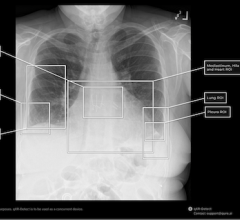

Advances in coronary CT angiography (CCTA) over the past two decades have helped cardiologists detect heart disease in ...

Advances in coronary CT angiography (CCTA) over the past two decades have helped cardiologists detect heart disease in asymptomatic patients more accurately. Now, providers are using dedicated cardiac ...